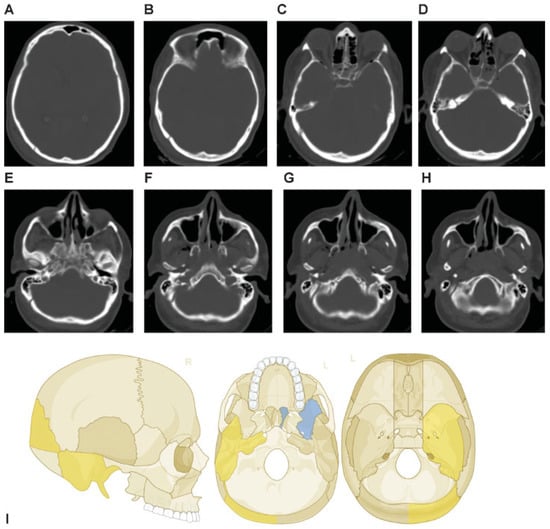

This coding system allows description of most relevant fracture patterns as illustrated in the case examples, such as the differentiation between unilateral or bilateral fracture patterns. In a series of three case examples, we illustrate the coding of a case with multiple cranial vault fractures (Figure 5), a single skull base fracture extending into the temporal cranial vault (Figure 6) and a right occipital and temporal cranial vault fracture extending into right middle fossa skull base (Figure 7). A range of additional fracture patterns are presented in a special case appendix as electronic supplement to this issue of the Journal (www.aocmf.org/classification).

Figure 7. Right occipital and temporal cranial vault fracture extending into the right middle fossa skull base. (A–C) Right occipital cranial vault fracture extending inferiorly into the right temporal bone, (D–H) with extension across the right middle fossa skull base through the skull base portion of the right temporal bone. There does not appear to be any fragmentation. (D) A probable left sphenoid fracture may be noted as well. Imaging: Computed tomographic axial views. (I) Level 3 code: 93 T0.M0.m.S, 94 O0.m, This case example CMTR-93-94-003 is made available electronically for viewing using the AOCOIAC software at www.aocmf.org/classification.